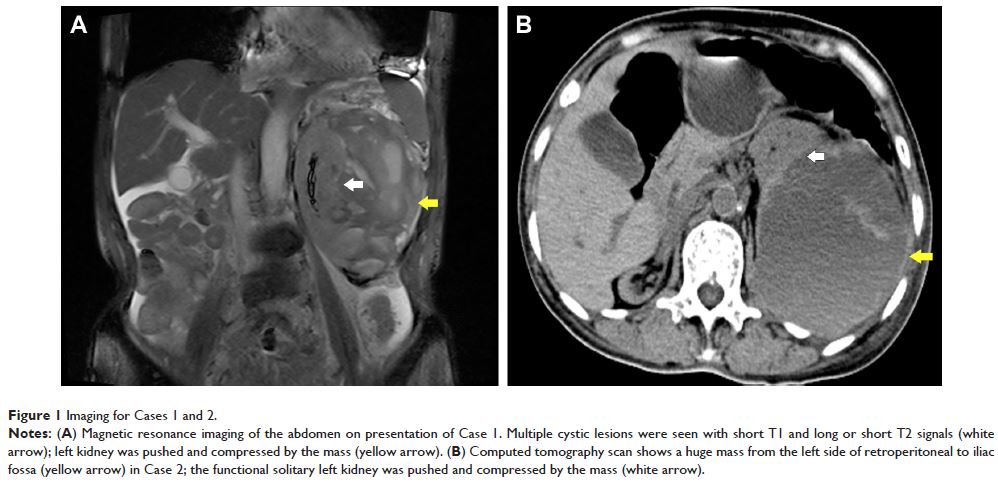

Case Series 简明总结

- 作者:Hao-Yuan Lu, Wei Wei, Qi-Wei Chen, Qing-Gui Meng, Gao-Hua Hu, Xian-Lin Yi, Xian-Zhong Bai

- 期刊:Therapeutics and Clinical Risk Management